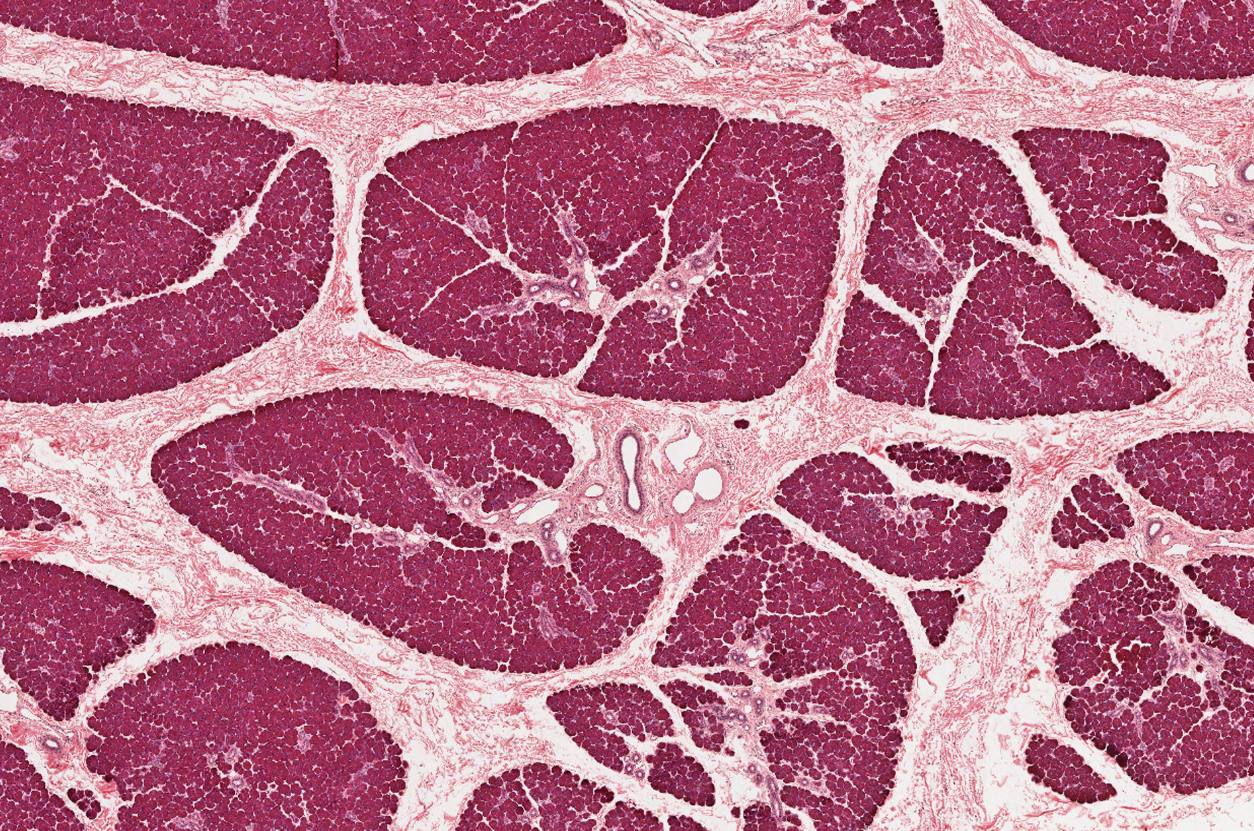

Salivary Gland

NOTICE: THE OPEN SPACES WHICH IS THE DUCTS THAT THE SECRETIONS ARE RELEASED THROUGH